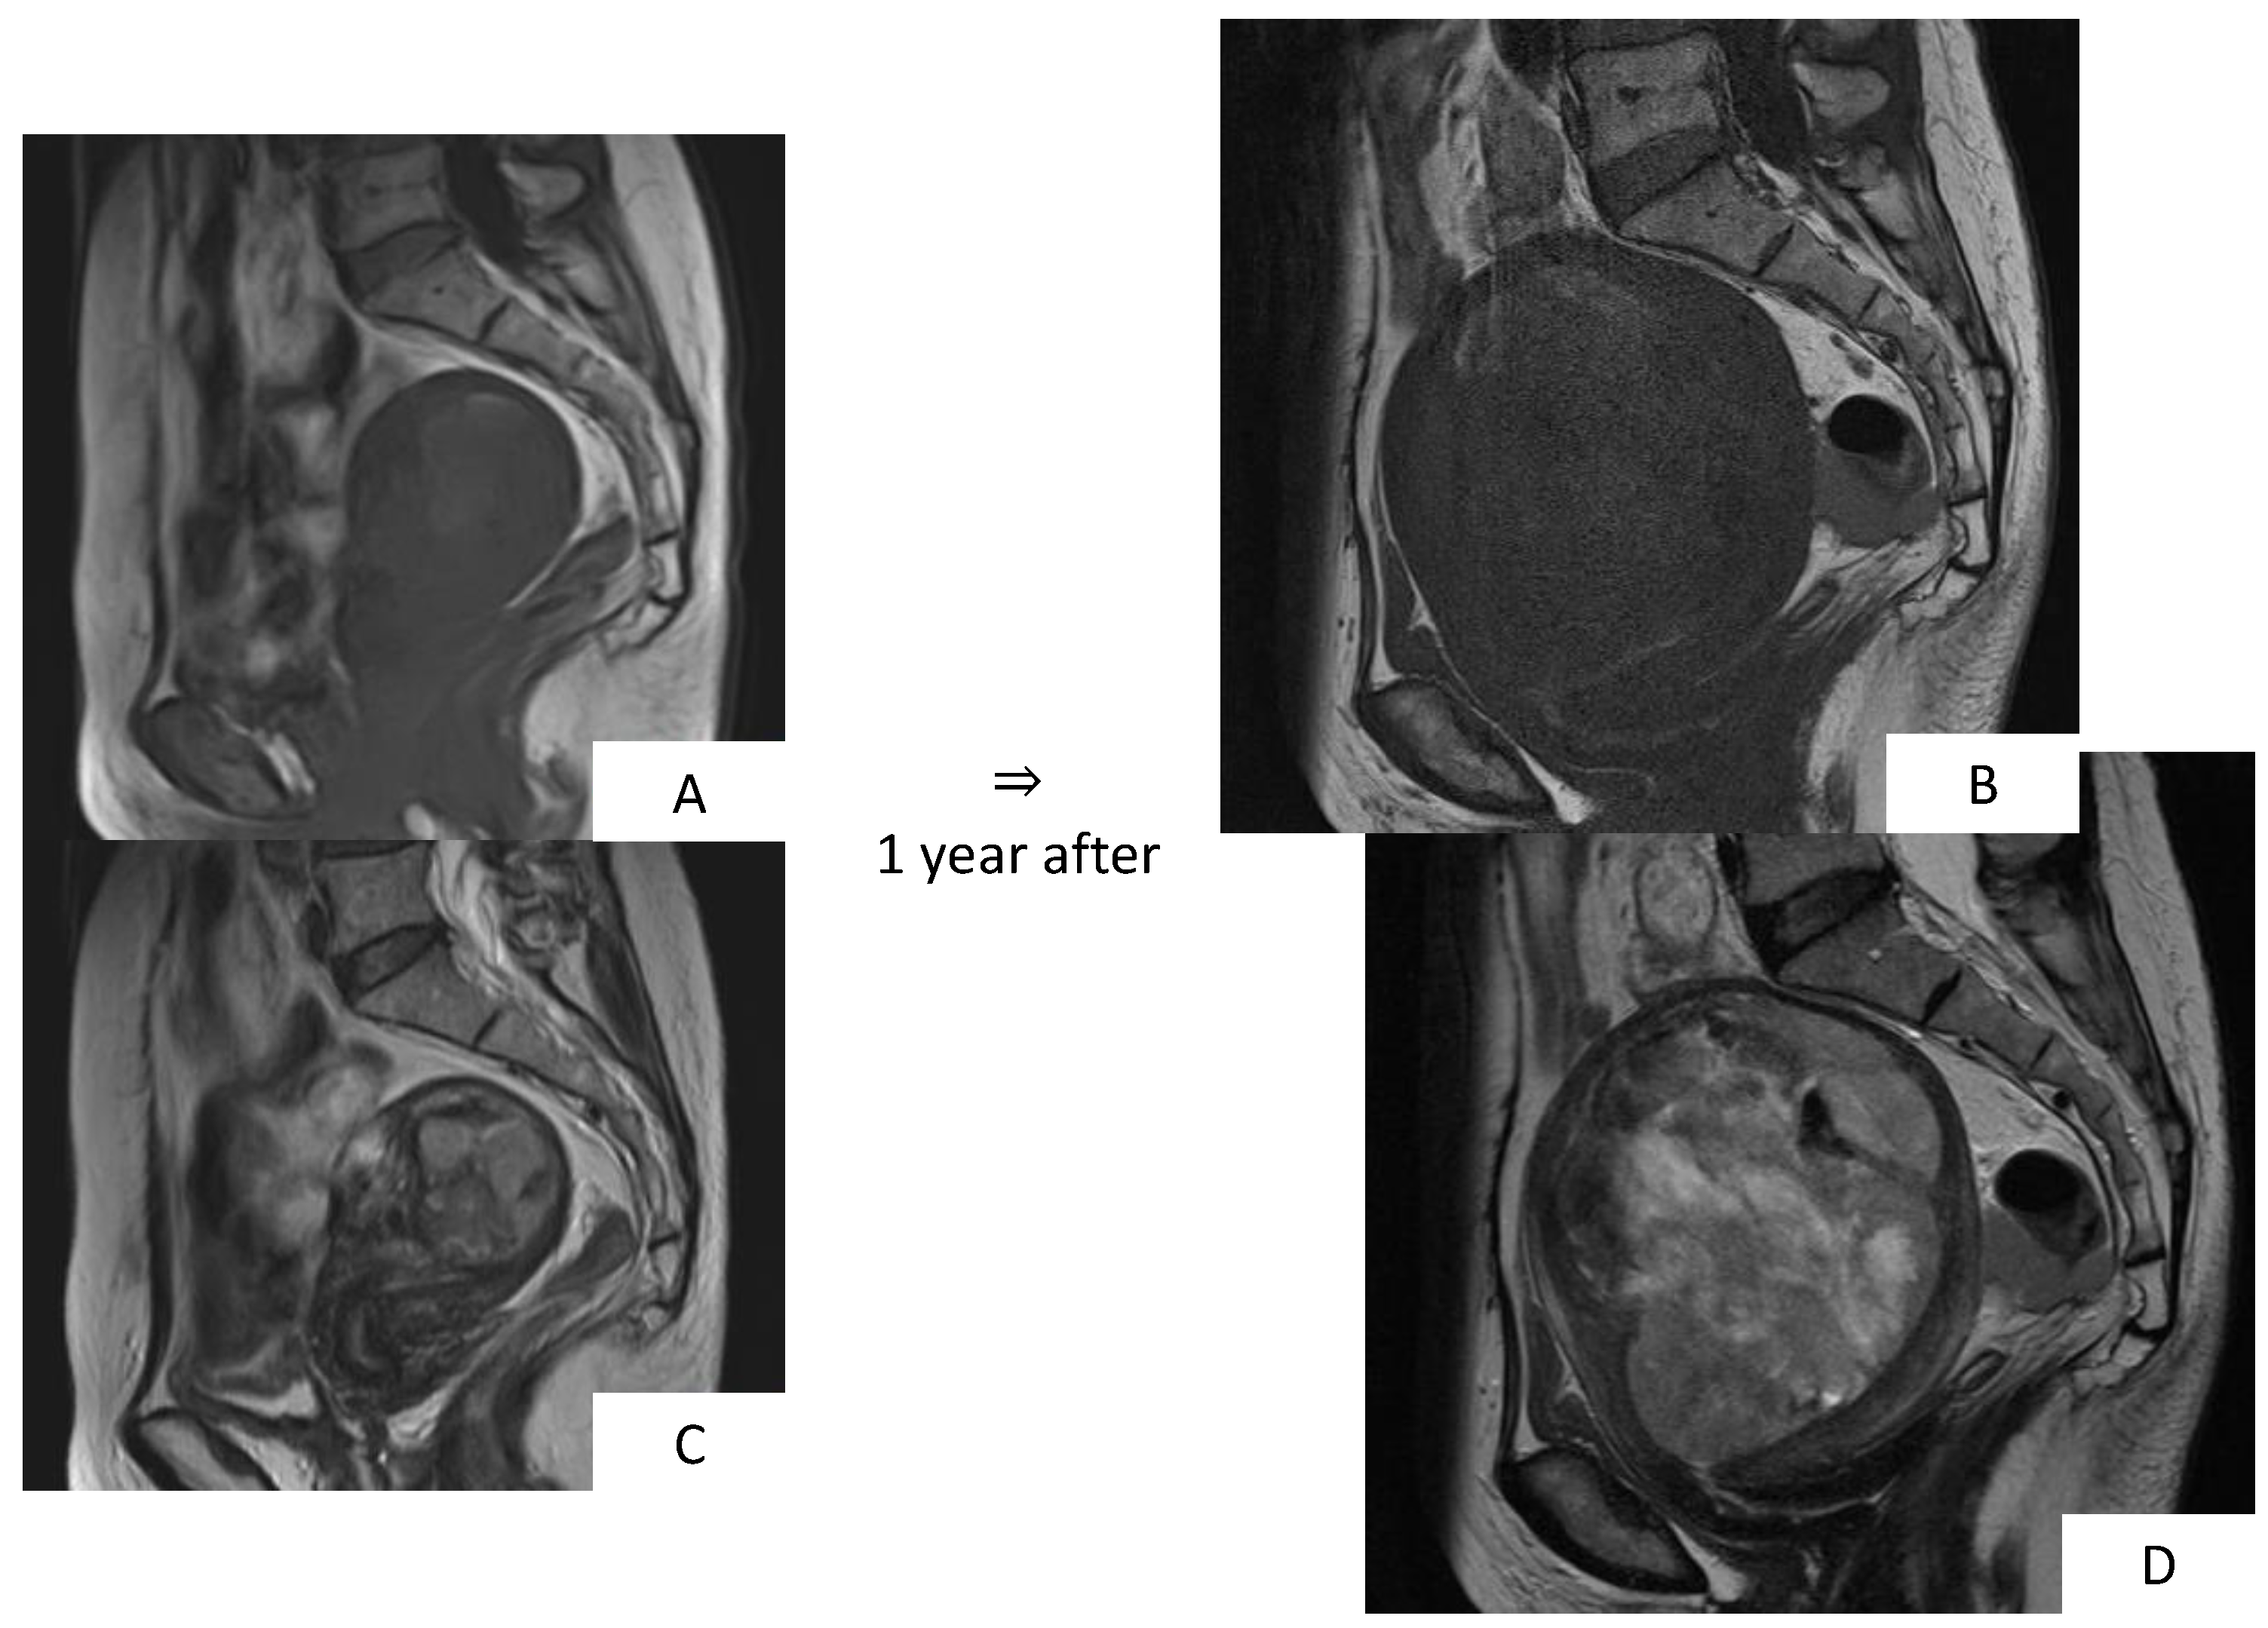

Figure 4.

Magnetic resonance images of leiomyosarcoma. (A,B): T1-weighted sagittal sections, (C,D): T2-weighted sagittal sections. In the myometrium, in T2-weighted images, overall, there is high signal intensity with ill-defined borders; in T1-weighted images, there is mass accompanied by internal hemorrhage. Follow-up observation was selected for this case, with the diagnosis of uterine sarcoma 1 year thereafter.